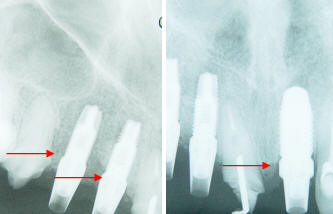

Foto 8:

Rx de control del asentamiento completo de los

pilares protésicos sobre los implantes. |